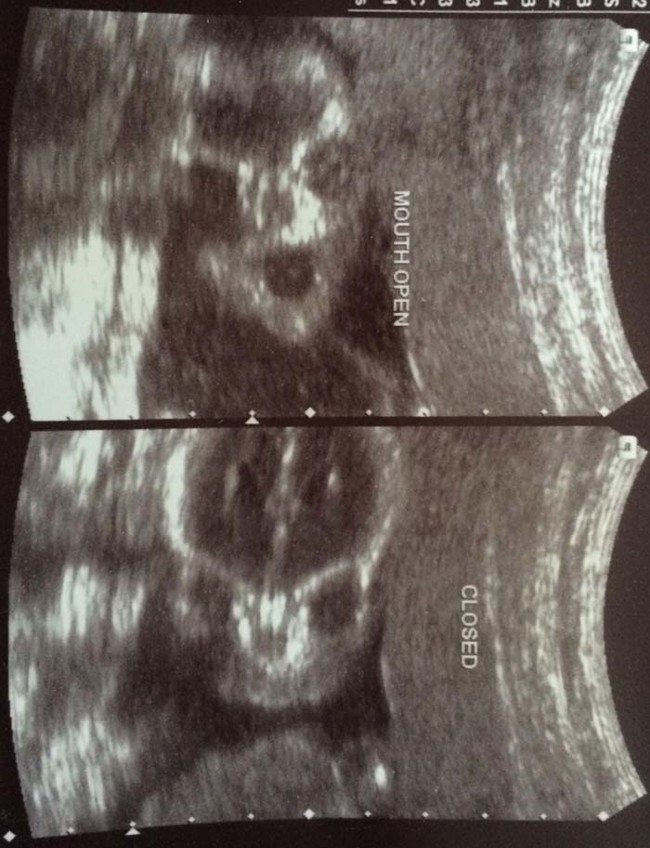

เดี๋ยวนี้ยามตั้งครรภ์คุณแม่เกือบทุกคนก็นิยมอุ้มท้องป่อง ๆ ไปให้คุณหมอทำอัลตราซาวด์ จะได้เช็กดูว่าเจ้าตัวน้อยข้างในอยู่สบายแข็งแรงดีหรือเปล่า แถมยังได้จะเห็นไปหน้าเค้าโครงใบหน้าลาง ๆ ของเจ้าหนูด้วย ดูแค่เงาก็เดาไปกันใหญ่แล้วว่าเหมือนใครมากกว่ากัน จนอดใจไม่ไหวอยากรีบคลอดออกมาให้เห็นหน้าลูกน้อยตัวจริงเร็ว ๆ แต่ถ้ามาเจอ 13 รูปอัลตราซาวด์สุดสยอง ที่เรานำมาฝากจากเว็บไซต์ boredomtherapy เหล่านี้เข้าไปหน่อยล่ะก็... บางทีคุณอาจไม่แน่ใจแล้วล่ะว่า นี่ใช่ลูกฉันจริงหรือเปล่า !!

ถึงจะรักเด็กแค่ไหน แต่ถ้าคุณขวัญอ่อนเราขอเตือนกว่าอย่าเลื่อนลงไปดูดีกว่านะ...